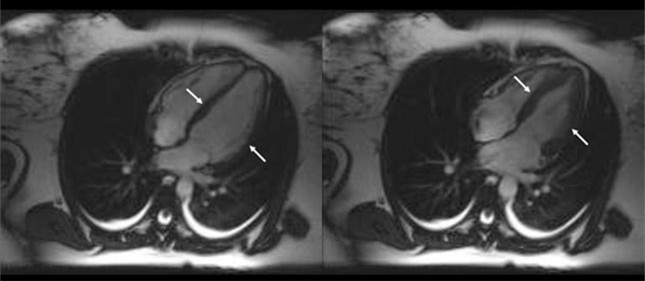

心脏收缩动态磁共振成像(MRI)显示了一名81岁TCM患者典型的心尖气球样扩张(A)。同一患者的心血管MRI(CMRI)T 2(横向弛豫时间)像显示心尖心肌T2信号强度升高[橙色](B)。这两个两腔位图像是在最初诊断TCM后3天获取的,患者在全身发作后出现短暂的心电图(ECG)改变和肌钙蛋白水平升高。

图像显示了81岁TCM患者发病3天后的两腔CMRI影像(幻灯片3是同一患者)。

左图:传统T2加权短时间反转恢复序列(STIR)快速自旋回波图像,可见心肌心尖信号强度增加,难以与缓流时管腔内血流信号进行区分。

右图:LGE 图像排除心肌瘢痕。